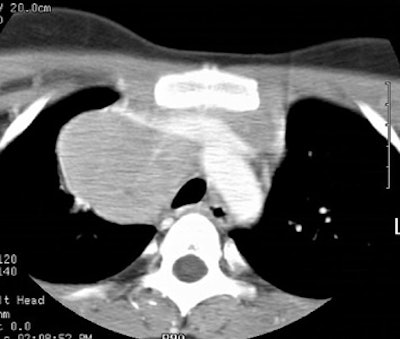

Computed Tomography: CT can detect intrathoracic sites of disease not detected on CXR in up to 20% of patients. The effect on patient management is quite variable (between 10-60% of patients), and is related to the specific protocol for which the patient is being considered. On CT there is usually an asymmetric, anterior mediastinal soft tissue mass which may invade the chest wall. Bulky mediastinal nodal disease can be associated with interstitial edema due to lymphatic/venous obstruction. Although typically homogeneous, larger masses may contain areas of decreased attenuation representing necrosis or cyst formation. Calcification is RARE prior to therapy. A pleural effusion is seen in up to 30% of cases and is usually felt to be related to lymphatic/venous obstruction from the mediastinal mass [ACR Syllabi #40:p.134 suggests effusions are found in only 2% of cases]. Benign pericardial effusions may also be seen in such patients.